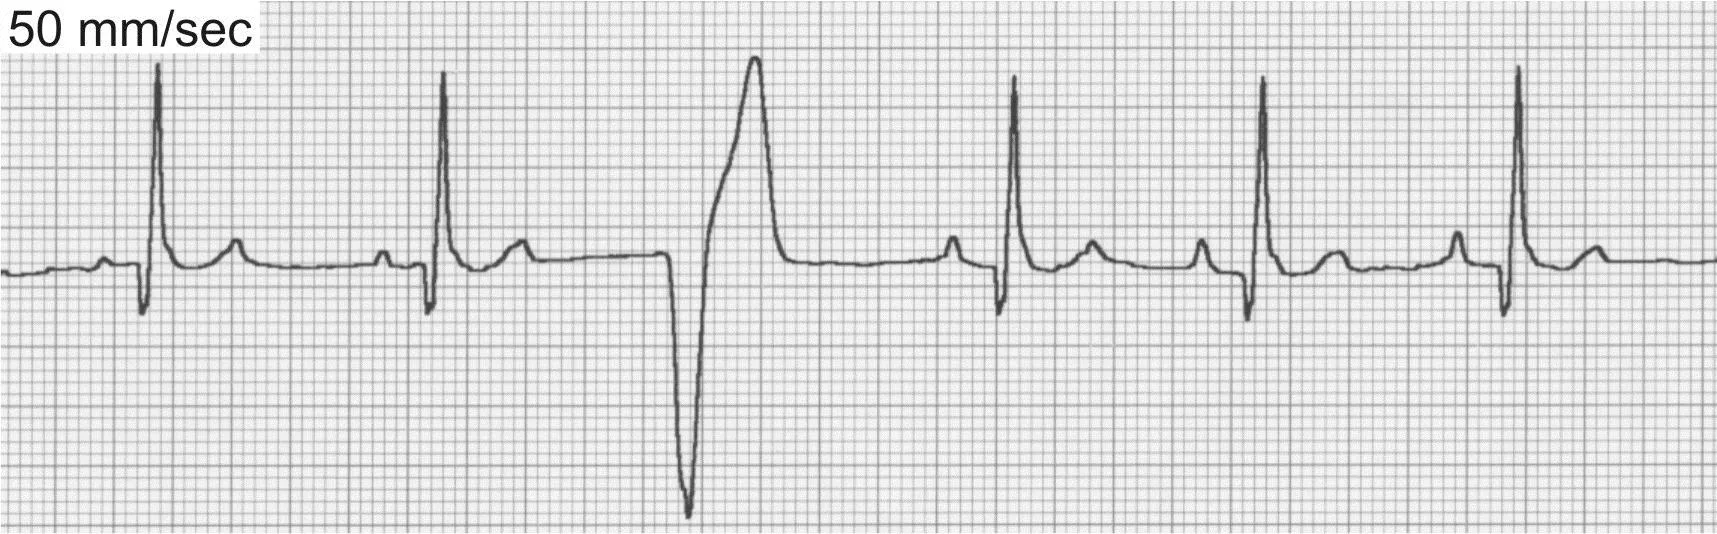

Sinus arrhythmia (Figure 3) is a phasic variation in heart rate in which R-R intervals often vary by >10%. There continues to be a P wave for every QRS complex and a QRS complex for every P wave, although on occasion the P wave morphology will vary or be difficult to visualize because of a phenomenon called wandering pacemaker (Figure 3B).

ECG of sinus arrhythmia

ECG of the wandering pacemaker phenomenon

Sinus arrhythmia is usually respiratory with the heart rate increasing in late inspiration and early expiration and decreasing in mid to late expiration. However, any other cause of increased vagal tone may also contribute to sinus arrhythmia even in the absence of respiratory variation. The underlying mechanism of sinus arrhythmia is depressed normal automaticity of the SA node.

Sinus arrhythmia is most common in normal resting dogs but uncommon in cats. Treatment is not required.